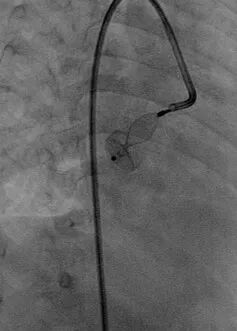

右侧股动、静脉入路。

术中造影提示左冠状动脉及回旋支明显增粗,回旋支发出一粗大的瘘血管与冠状静脉窦联通,瘘口处存在多处狭窄。